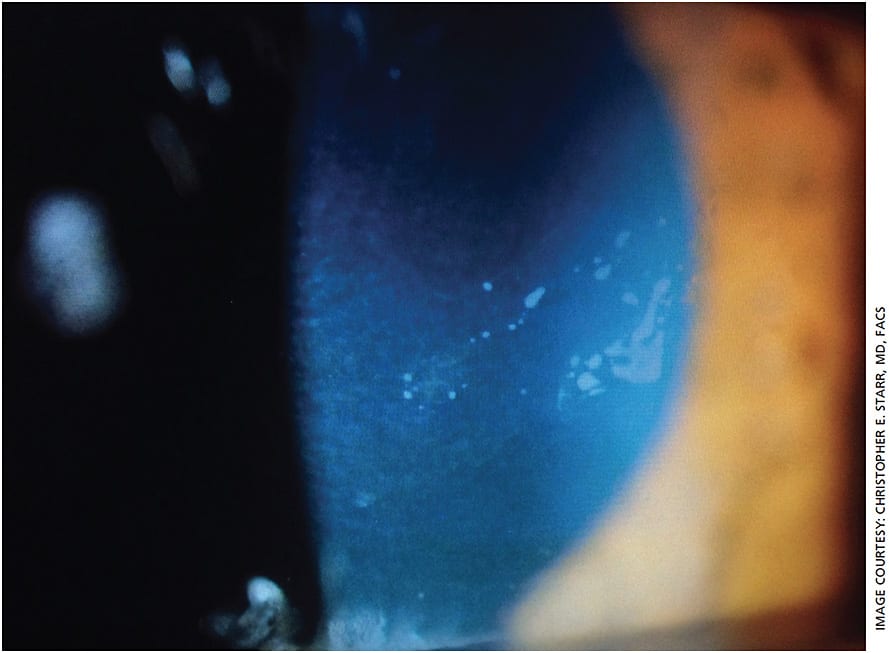

- Corneal and conjunctival staining. Performed with fluorescein and/or lissamine (green), this is a traditional and inexpensive test but also an effective and reliable way to assess the health of the ocular surface, including the quality of the tear film (Figure 1). Subtle corneal pathology, such as anterior basement membrane dystrophy (Figure 2), can also be identified with fluorescein, in addition to punctate staining of the cornea and conjunctiva.

Figure 1. Fluorescein dye reveals punctate epithelial erosion, a common cause of dry eye symptoms.